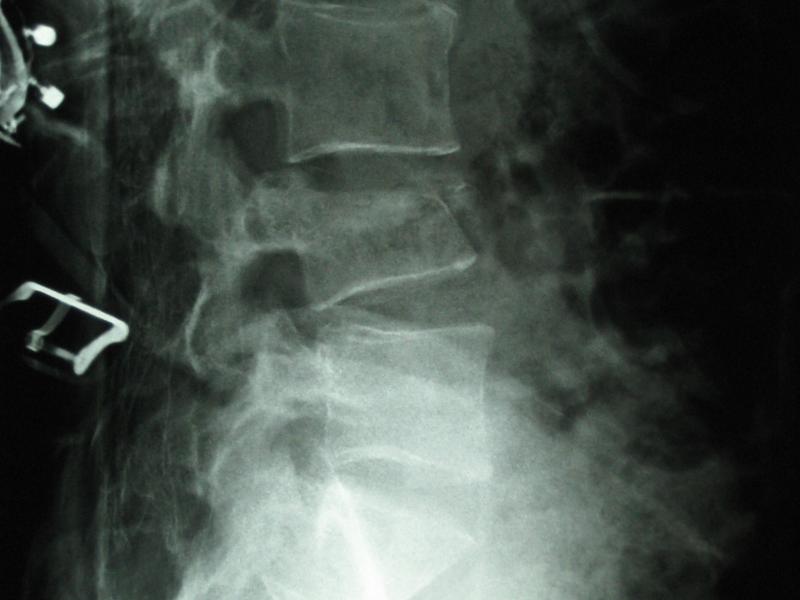

Orthopedic Injuries Around the NFL: Tony Romo's Lumbar Spine Compression Fracture

During a preseason exhibition game of this NFL season